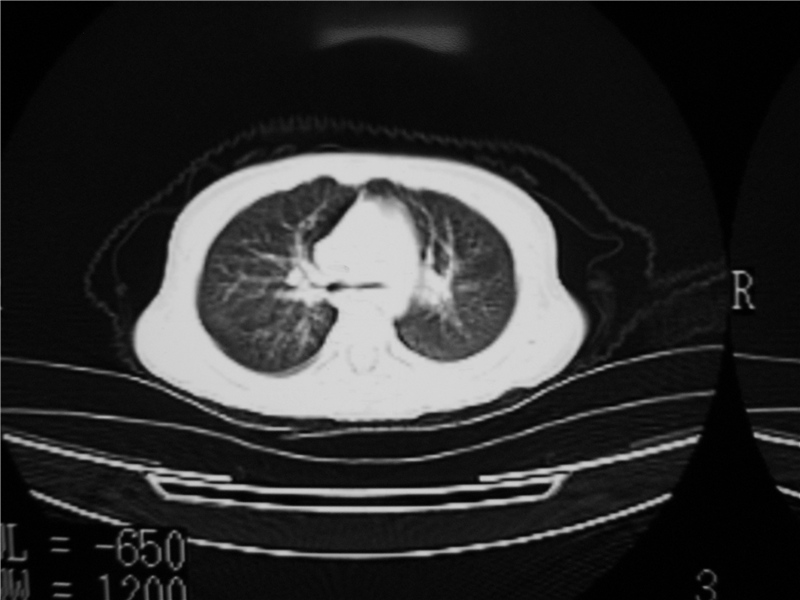

1)右肺炎症并右肺中叶肺不张,右肺上叶充气不良。2)右侧支气管异物不排除。

右肺炎症并右肺中叶肺不张,右肺上叶充气不良。2)右侧支气管异物不排除。